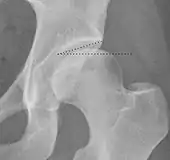

Projectional radiography ("X-ray")is often considered first line for FAI.[10] Anterior-posterior pelvis and a lateral image of the hip in question should be attained.[10] A 45-degree Dunn view is also recommended.[10][19]

| Tönnis angle | ![]() |

Slope of the sourcil (the sclerotic weight-bearing portion of the acetabulum) | 0 to 10°

|

| Caput-sourcil angle[21] | ![]() |

Superior to the Tönnis angle in cases without joint space narrowing or subluxation.[21] The medial point of the sourcil is at the same height as the most superior point of caput femoris. | −6 to 12°[21]